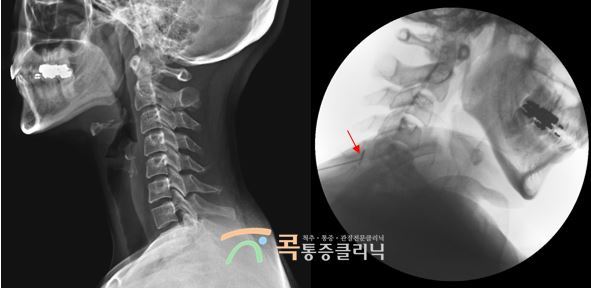

경추성 두통을 진단받은 20대 남성 환자분

1.jpg

몇 달째 지속되었던 심한 두통으로 인해서 콕통증클리닉을 찾으셨습니다. 두통과 함께 안압이 올라서 눈이 빠질 듯 아픈 느낌, 어지러움, 속이 메스꺼운 증상 등으로 일상생활이 힘드시다고 호소하셨어요. 내원 당시에는 진통제를 섭취해도 그때뿐이고 두통 증상이 쉽게 호전되지 않는다고 힘들어하셨습니다.

두통의 증상은 일상생활을 하실 때 목이 점점 뻐근해지면서 두통이 수반되는 것이었습니다. 전형적인 경추성 두통의 증상으로 확인되어서 후두신경치료를 통해 직접 신경 치료를 시행하고, 바른 자세 스트레칭을 통해 자세 교정도 함께 진행되었습니다.